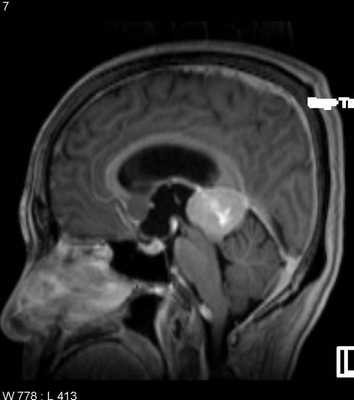

МРТ головного мозга. Менингиома свободного края намета мозжечка (область шишковидной железы). Сагиттальные Т1-зависимые МРТ до и после контрастирования.

Менингиома может развиться из любого участка стенки задней черепной ямки, но чаще из свободного края намета мозжечка и в области большого затылочного отверстия. Эти менингиомы при МРТ головного мозга имеют те же черты, что и характерные для супратенториальных менингиом. Дополнение стандартной МРТ МР-венографией помогает выявить компрессию поперечного синуса.

МРТ головного мозга. Менингиома задней черепной ямки. Аксиальная Т1-зависимая МРТ с контрастированием.